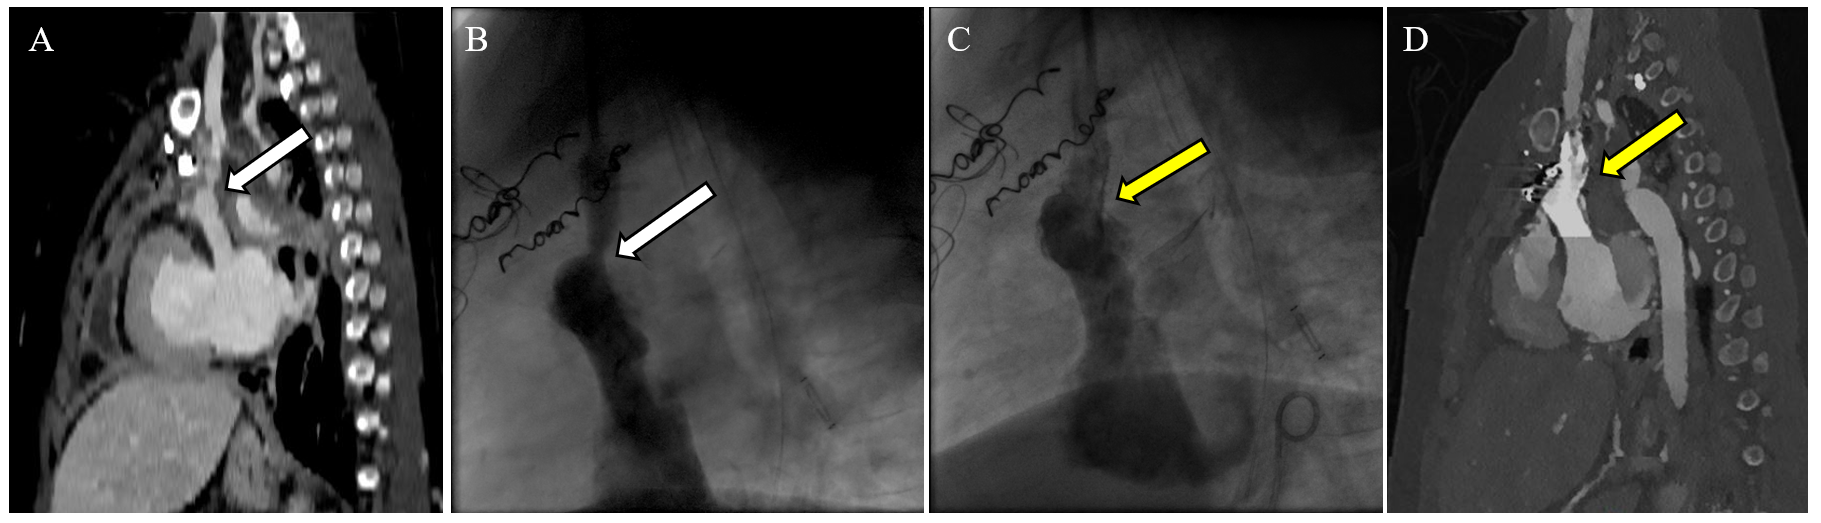

Figure 3 illustrates the utility of multimodality imaging in a 16-year-old girl with a complex heterotaxy syndrome and PLE from the case series by Alaeddine et al.4 MRL revealed TD drainage into the right internal jugular vein (IJV), which in turn connected to the left SVC—an unusual anatomical variant necessitating modification of the surgical approach. Postoperative computed tomography (CT) angiography demonstrated the surgical reconstruction used based on this information (Figure 3, panel B). The surgery involved transection of the left IJV from the left SVC with oversewing of the distal stump, detachment of the left SVC from the left pulmonary artery (LPA), and reconstruction of the superior cavopulmonary anastomosis (Glenn anastomosis) using a 14 mm Gore-Tex (W. L. Gore & Associates) interposition graft between the left IJV and the LPA. The left SVC was anastomosed to the left atrial appendage, with enlargement of the anterior-left anastomotic aspect using a bovine pericardial patch.4

Figure 3: Pre- and Postoperative CT Angiograms in a Complex Case

Figure 3

Preoperative angiogram (panel A) and postoperative CT angiograms (panels B, C) in a complex case of a patient with heterotaxy syndrome, dextrocardia, left-sided SVC, TD draining into the right-sided IVJ, and recurrent PLE. The surgical technique for turndown was modified on the basis of the patient's systemic venous anatomy. (Panel A) Preoperative CC. AP projection of an angiogram showing a left-sided SVC (orange arrow) with cavopulmonary anastomoses (Glenn anastomoses). The white arrow indicates the right InV and the green arrow indicates the LPA. (Panels B, C) The AP view (panel B) and left-sided view (panel C) on postoperative CT angiograms of the same patient with 3D reconstruction after an InV turndown procedure. The right InV (white arrows) and left SVC (orange arrow in panel B) are seen draining into the left-sided atrial appendage (yellow arrows). An interposition graft (blue arrows) was used to reconstruct the Glenn anastomosis by connecting the left IJV to the LPA (green arrow in panel C).

3D = three-dimensional; AP = anteroposterior; CC = cardiac catheterization; CT = computed tomography; InV = innominate vein; IVJ = internal jugular vein; LPA = left pulmonary artery; PLE = protein-losing enteropathy; SVC = superior vena cava; TD = thoracic duct.